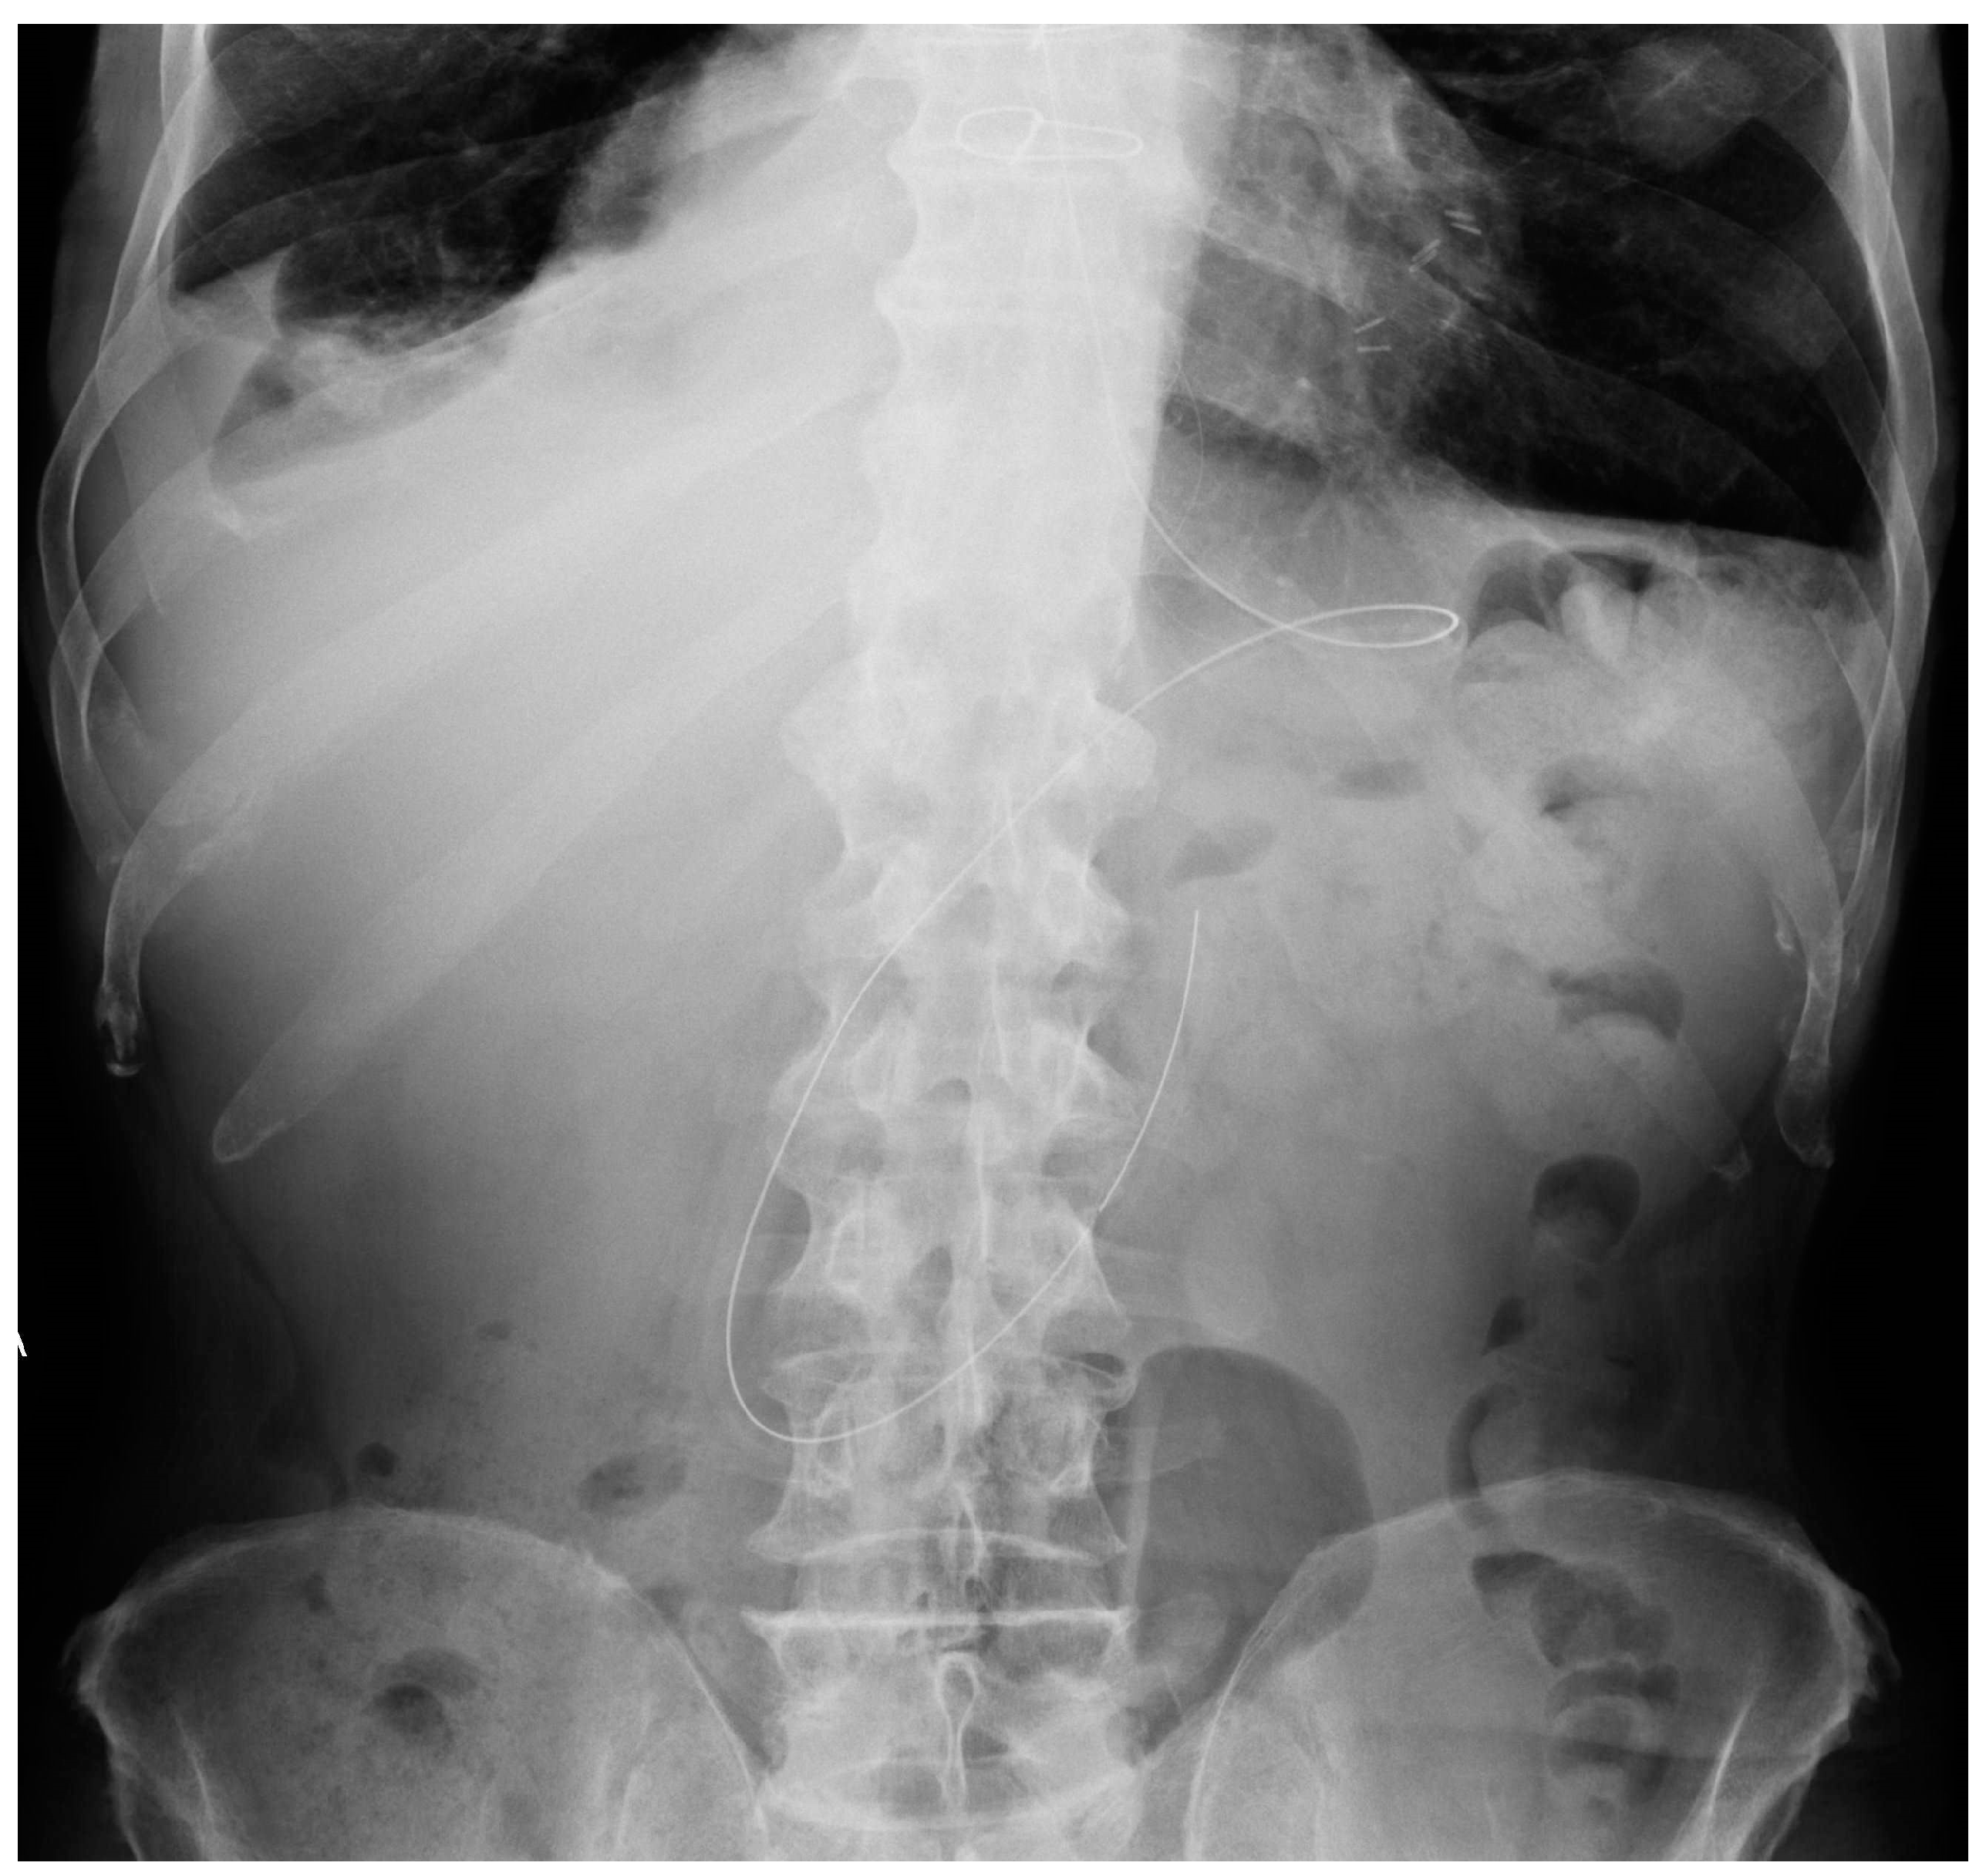

The most common CXR-detectable complications are pneumothorax, malposition (looping, inferior vena cava (IVC) positioning of the tip, wrong thoracic vein positioning), or, less often, vascular perforation, with the catheter located inside the thorax (Figure 3, Figure 4 and Figure 5, Table 2) [6,7].

Mispositioned CVCs. (a) Left jugular-inserted CVC with its tip inside the left axillar vein (white arrows). (b) Right jugular CVC with its tip inside IVC (red arrows). Note that due to underexposure during acquisition of the CXR, the tip of the catheter is hard to see in the upper abdomen.

Malpositioned CVCs. (a) Right jugular-inserted CVC looping against the vessel wall and ending inside the SVC (red circle). (b) Left jugular CVC with tip ending inside the right subclavian vein (red arrows).

A detail of a CXR showing a left jugular CVC looping with tip ending in the left jugular vein (green circle). Note that due to the underexposure of the CXR, the device is difficult to detect.